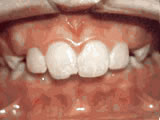

Teeth Crowding

Treated with braces for 26 months, starting at age 11 — now enjoying a confident new smile.

Teeth Crowding before Teeth Crowding after